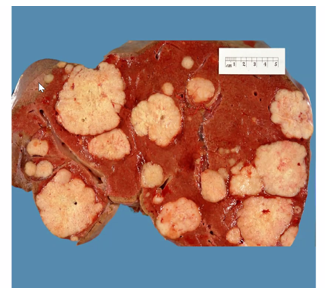

describe the specimen

Can see multiple large, pale, well circumscribed lesions. Centre is necrotic – soft and cheesy. High met load.

Wont be a candidate for curative treatment – need to include onchologists and see if palliative chemo

If one or 2 mets – metastasectomy